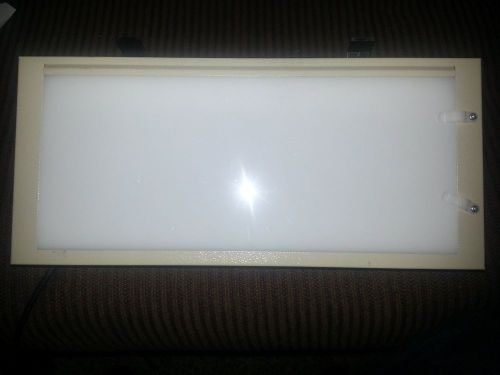

American Medical Sales Single Bank X-ray Viewing Box Illuminator Viewer

American Medical Sales X-ray Viewing Box Illuminator Viewer

Star X-ray Illuminator 100 Slimline 100v Beige #DE100BG

Star Xray Dental X Ray View Boxes Lot Of 3